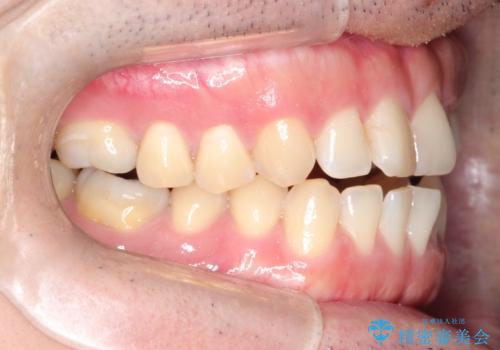

- 20代男性

- インビザライン

- 1年5ヶ月

- 10-30回

- 88万円費用は治療当時の料金となります